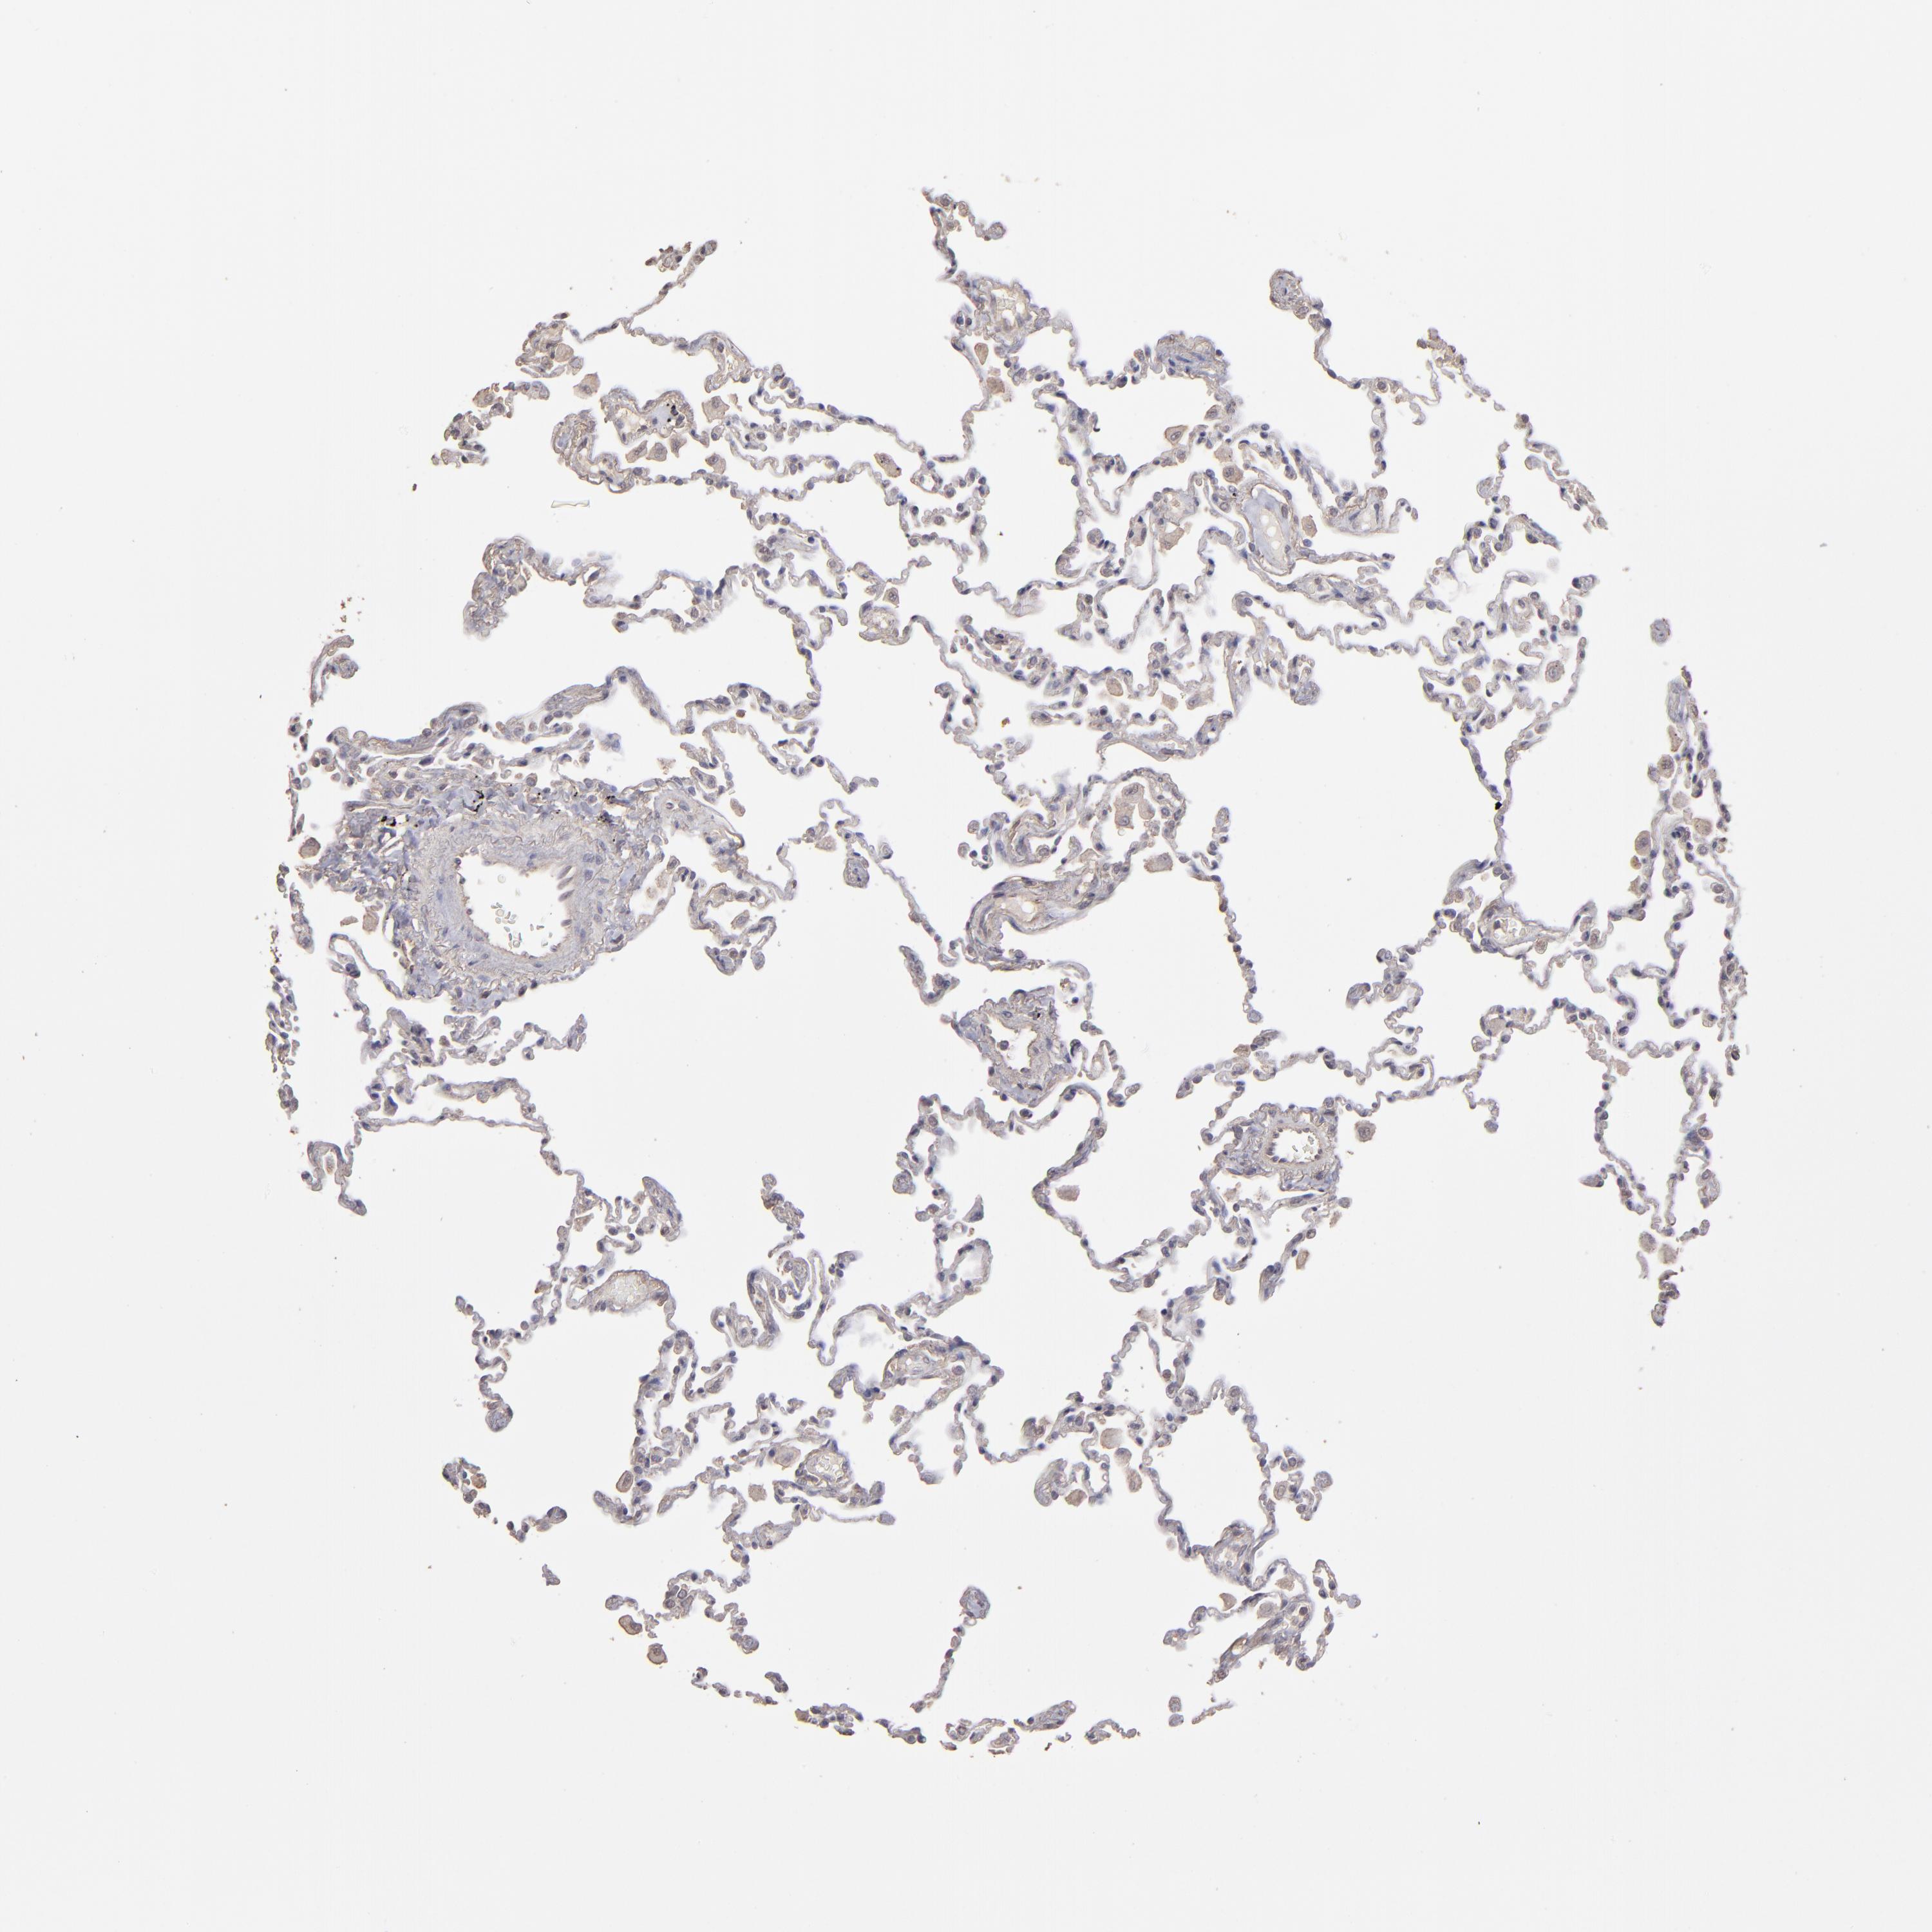

LUNG - Antibody stainingi

Antibody staining in the annotated cell types in the current human tissue is reported as not detected, low, medium, or high, based on conventional immunohistochemistry profiling in selected tissues. This score is based on the combination of the staining intensity and fraction of stained cells.

Each image is clickable and will lead to virtual microscopy that enables deeper exploration of all samples and also displays staining intensity scores, fraction scores and subcellular localization as well as patient and tissue information for each sample.

Antibody HPA001869Antibody HPA023882

Alveolar cells Not detectedMedium

Macrophages LowMedium